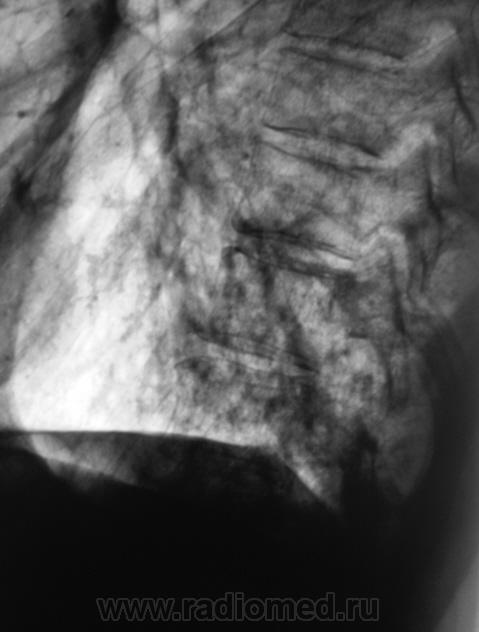

Пациент направлен на рентгенографию ОГК с диагнозом - "Левостороняя пневмония".

Анамнез стандартный. Ранее неоднократно страдал обострениями хронического бронхита. Сейчас вот не нашутку занемог - температура до 38, откашливает мокроту, кашель продуктивный.

Диагноз левосторонней нижнедолевой С10, С9 сементарной пневмонии наверное будет верным, а с учётом фона- с наличием бронхоэктазов.